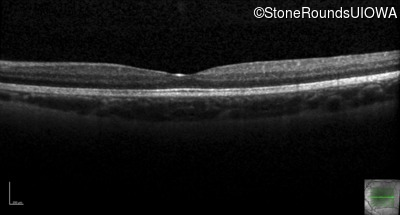

Optical Coherence Tomography - Right - 20/50

Exemplar / OCT Stack